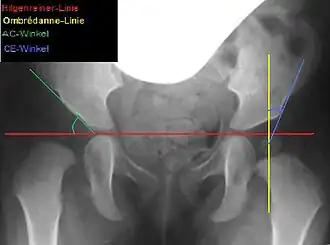

Lateral coverage is measured using the acetabular angle (AC angle) on a pelvic X-ray, defined as the angle between a horizontal line through the Y-sutures and a line along the acetabular rim. In healthy newborns, the AC angle is approximately 25°, decreasing to about 15° by age 6 and 11–12° by age 12.[6] Acetabuloplasty aims to correct the AC angle to these physiological values, achieving an anatomical reconstruction.[6]